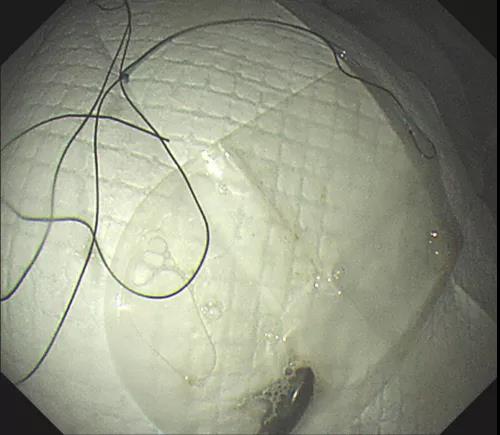

经过充分的术前准备,该院内镜外科副主任胡健聪对小逸进行镇静镇痛胃镜检查。胃镜下见到胃腔内残留大量韭菜残渣,唯独看不到磁铁。“一般而言,胃的排空时间为4-6个小时”。因此,胡健聪认为磁铁仍然在胃里面,只不过是被食物残渣覆盖。通过胃镜下的异物钳,分次把韭菜残渣完全取出,磁铁终于暴露在胃镜之下。

磁铁难夹,医生“包饺子”取出

胡健聪尝试用异物钳、圈套器等常规取异物器械,发现都没有办法把磁铁夹住取出。他立即联系手术室,借用手术室腹腔镜常用的无菌标本取出袋,在袋子上绑上丝线,再通过胃镜把标本袋带入胃腔,通过异物钳慢慢像“包饺子”一样把磁铁推入标本袋,最后牵拉丝线经过嘴巴终于把磁铁完整取出。

磁铁顺利进入标本袋。